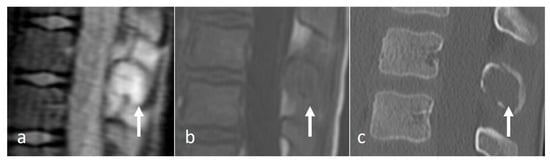

Figure 2.

Sagittal STIR (a) and CT (b) images demonstrating a thoracic spinous process osteoid osteoma (white arrows). Note the presence of reactive marrow oedema on the STIR sequence. The sclerotic reactive bone is well delineated on CT, although the lucent nidus may not always be present as in this case.